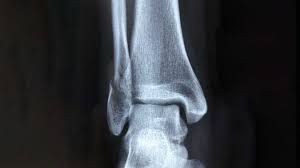

Fraktur oberhalb der verletzen Syndesmose Membrana interossea häufig auch rupturiert Die Maisonneuve-Fraktur wird als Sonderform der Sprunggelenksfraktur auch als Weber C klassifiziert. This normally takes approximately 6 weeks to heal. Die Weber-Klassifikation eine Methode zur Beschreibung von Sprunggelenksfrakturen.

KLASIFIKASI FRAKTUR WEBER Drsimon ponco septiono f Weber A Garis fraktur berada dibawah syndemiosis thibiofibularis f Weber B Garis fraktur berada setinggi syndemiosis thibiofibularis f Weber C Garis fraktur berada diatas syndemiosis thibiofibularis f. Weber C Fraktur immer Weber A- und Weber B- Frakturen mit. Many translated example sentences containing Weber c Fraktur English-German dictionary and search engine for English translations.

Weber C Fraktur. Neben der Weber C Fraktur gibt es auch noch die Fraktur der Klasse A und B. Was ist eine Weber-C-Fraktur. DayZ sa well kit DayZ Expansion Building Kits - YouTub. Verschobenem Bruch dislozierte Fraktur undoder. It has a role in determining treatment. Weber C Fraktur. Look up the French to German translation of weber c fraktur in the PONS online dictionary. The Weber ankle fracture classification or Danis-Weber classification is a simple system for classification of lateral malleolar fractures relating to the level of the fracture in relation to the ankle joint specifically the distal tibiofibular syndesmosis.